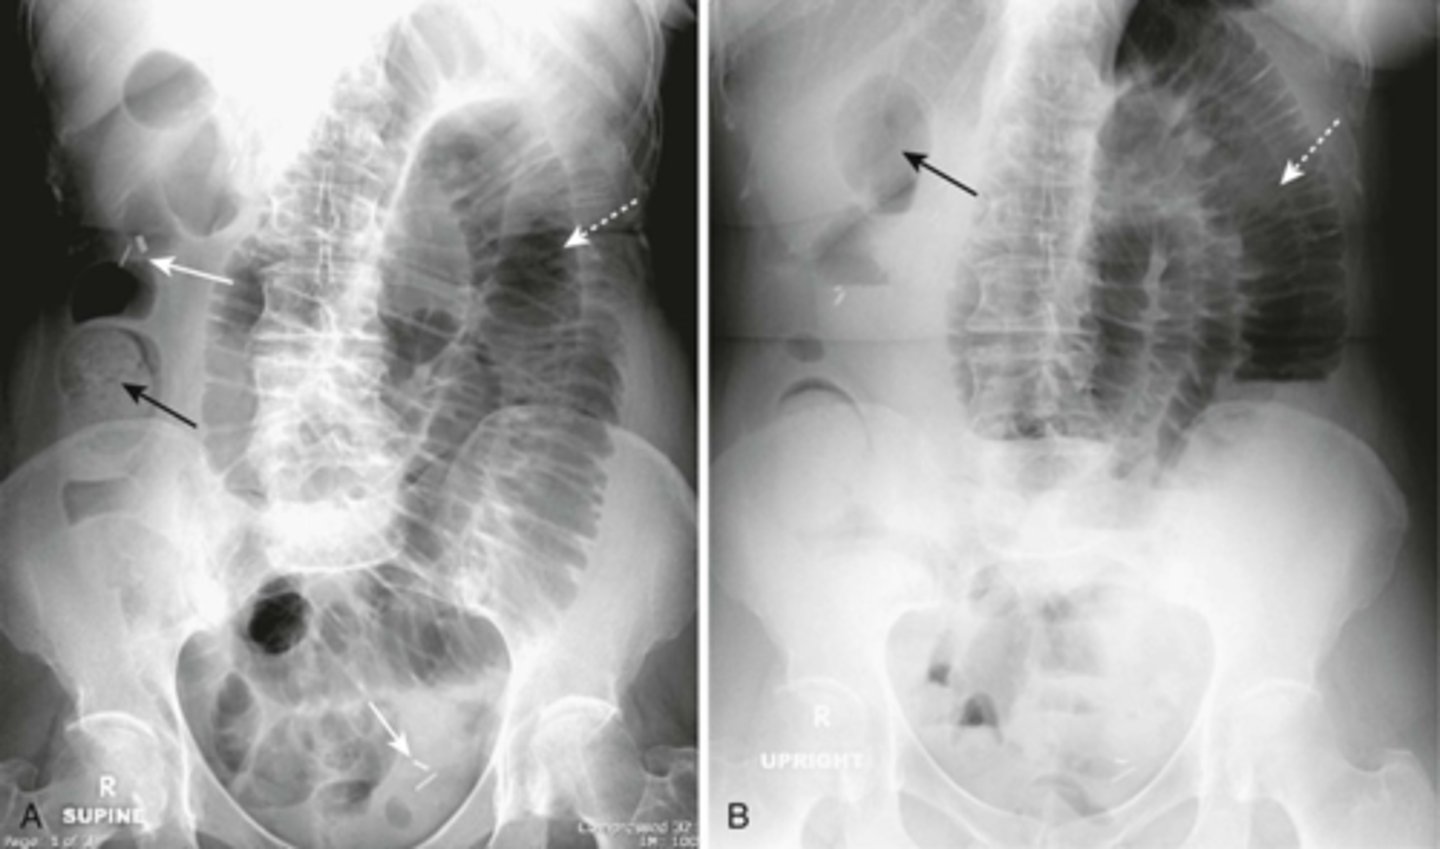

Localized ileus (sentinal loop) A: supine, B: prone

WHITE ARROWS: single, persistently dilated loop of Small Bowel in LUQ - representing a sentinel loop or localized ileus.

Often signifies the presence of an adjacent irritative or inflammatory process. This pt had acute pancreatitis

Generalized adynamic ileus, supine (A) and upright abdomen (B).

SOLID WHITE ARROWS: dilated loops of large bowel

DOTTED WHITE ARROWS: dilated loops of small bowel

SOLID BLACK ARROW: Rectum

Gas seen from small bowel to rectum. Patient had no bowel sound and had colon surgery the day before.